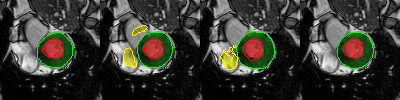

Careful inspection reveal that errors are not uniformly distributed. Interestingly, conv-deconv and U-Net produce accurate results on most slices of each 3D volume as illustrated in the first two rows of Fig. 2. That said, they often get to generate a distorted result for 1 or 2 slices (out of 7 to 17) which end up decreasing the Dice score and increasing the Hausdorff distance. This situation is shown in rows 3,4, and 5 of Fig. 2. Overall, the right ventricle is the most challenging region for all three methods. It is especially true at the base of the heart, next to the mitral valve where the RV is connected to the pulmonary artery. This is illustrated in the last row of Fig. 2.